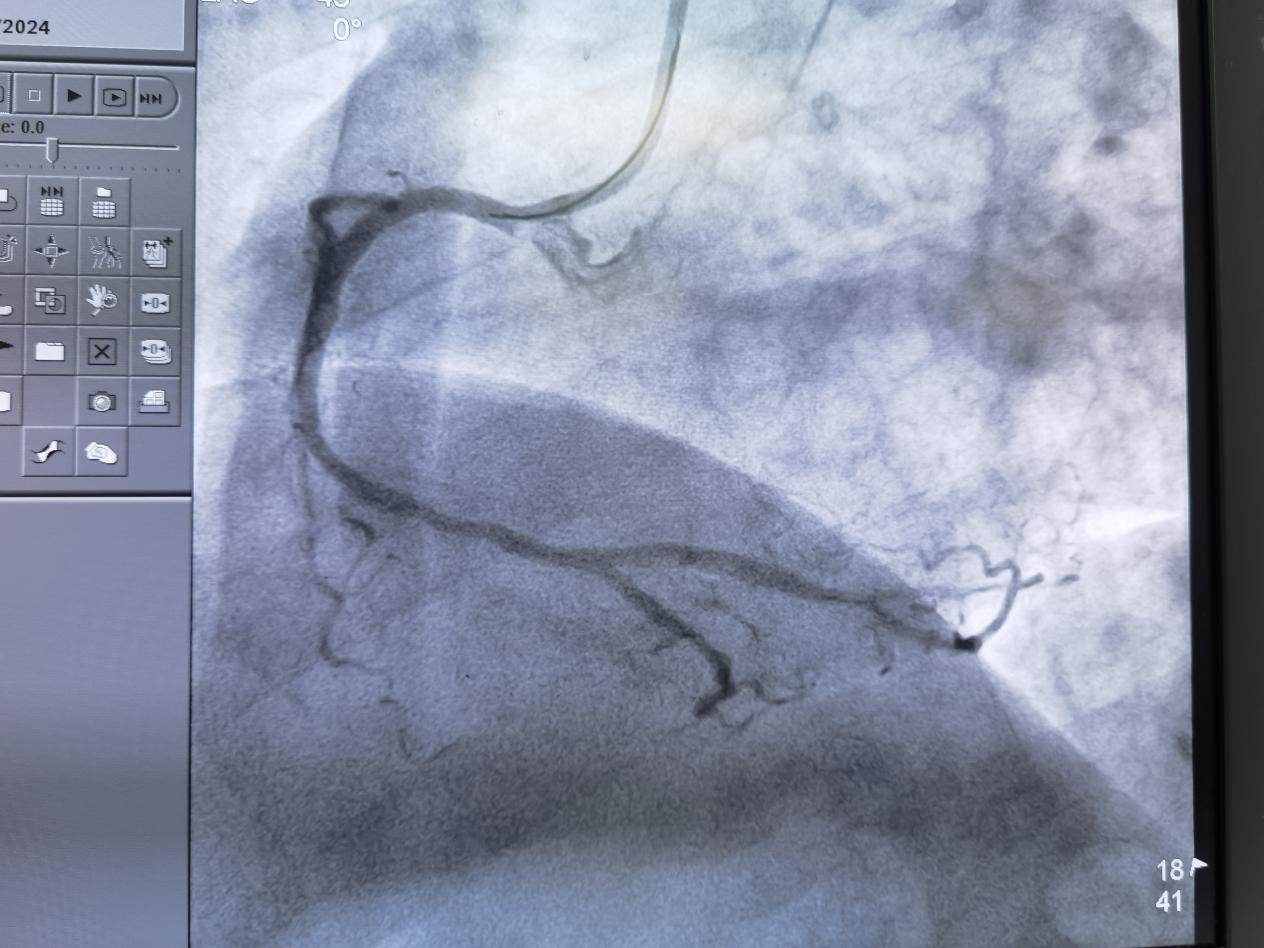

导管室外,家人焦急等待,祈祷着生命的奇迹。导管室内,心血管内科专家团队严阵以待,用精湛的技术和丰富的经验,在导丝指引下,支架顺利抵达“目的地”,闭塞的血管瞬间畅通,心肌的血流灌注恢复了,刘先生终于重获新生!

成功开通血管

手术中